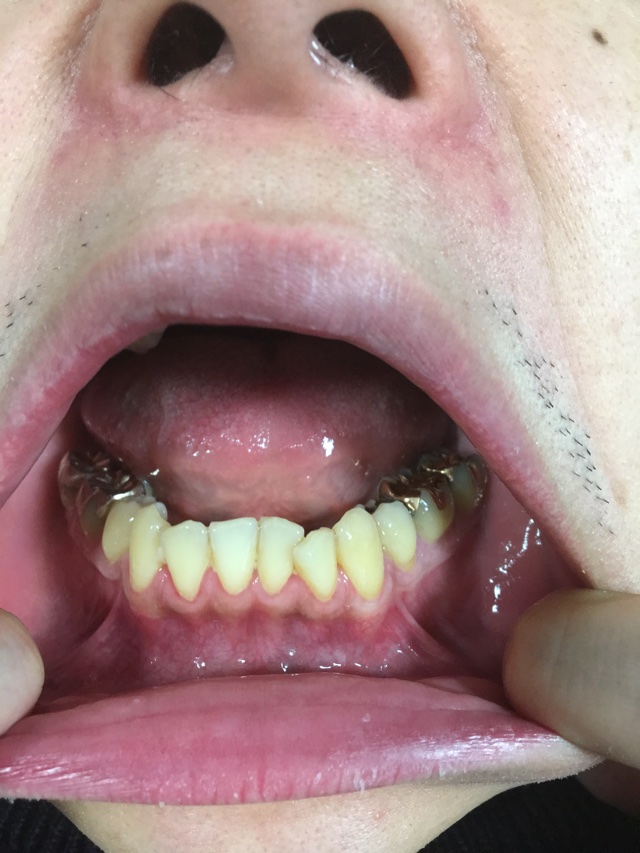

(因みに特にこの2年半での歯茎後退と歯の伸びは写真の程度です。)

画像1IMG_0384.JPG 画像2IMG_0386.JPG

ネットではお写真を見て、診査診断できませんので、なんとなぁ〜くの回答になります。

個人的には

「極端に下がっているようには見えないなぁ」

「でも汚れているから、歯周病とかが心配になるんじゃないかなぁ」

「歯医者さんでしっかりクリーニングを受けたほうがいいんじゃないかなぁ」

みたいな感じでしょうか。